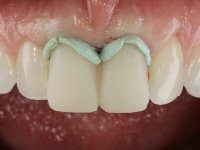

Paciente do sexo feminino com 41 anos de idade, não fumadora. Apresentava duas coroas sobre espigões falsos cotos fundidos nos dentes 1.1 e 2.1. As coroas apresentavam-se com infiltrações cervicais com exposição da superfície radicular. A papila gengival mediana, apresentava-se ligeiramente retraída. O espaço mesio-distal correspondente às duas coroas mostrava-se alto e estreito. Apresentava um ligeiro apinhamento dos incisivos inferiores, bem como uma pequena retração gengival. No sorriso era bem visível a zona cervical das coroas, mostrando um aspeto acinzentado correspondendo ao escurecimento radicular. No exame imagiológico verificou-se que o tratamento endodôntico não estava tecnicamente satisfatório, mas assintomático à quase 10 anos.

O tratamento iniciou-se com a confeção de moldeiras transparentes em silicone para aplicação de peróxido de carbamida a 16%. Os espaçadores colocados na superfície vestibular foram cuidadosamente preparados em resina nos modelos de gesso. O tratamento foi feito aplicando o produto 2 horas por dia durante 8 dias. Após o branqueamento esperamos 4 semanas e iniciamos o tratamento prostodôntico. Foi realizada uma pré-impressão em silicone para confeção de uma ponte provisória com resina composta de polimerização dual. Em seguida iniciamos a remoção das coroas. Foi feito um corte vertical na zona média da coroa até encontrar a superfície do espigão falso coto fundido. No bordo incisal também foi realizado o mesmo corte. Em seguida com um luxador fino foi feita a separação das partes distais das coroas. Para a remoção das partes mesiais foi feito um corte na linha média abrangendo ambas as coroas. No final da remoção atraumática das coroas antigas os cotos foram re -preparados. Na re-preparação dos cotos a linha de acabamento foi colocada a nível intra-sulcular. Na mesma consulta foi feita a impressão definitiva. O afastamento gengival foi realizado com a técnica da pasta de caolino comprimida pela ponte provisória.  A impressão foi feita pela técnica de dupla mistura com dupla viscosidade com silicone de presa rápida. No laboratório foram confecionadas 2 coroas com infraestrutura em Zr sendo revestidas a cerâmica. No sentido de evitar aparência de coroas “muito altas” foi aumentado ligeiramente o diâmetro mesio-distal sobrepondo-se ligeiramente aos dentes adjacentes. A ponte provisória foi removida os cotos foram polidos e as coroas foram colocadas para verificação final. Confirmado o seu ajuste e aprovadas pela paciente foram cimentadas definitivamente com cimento de ionómero de vidro reforçado com resina.